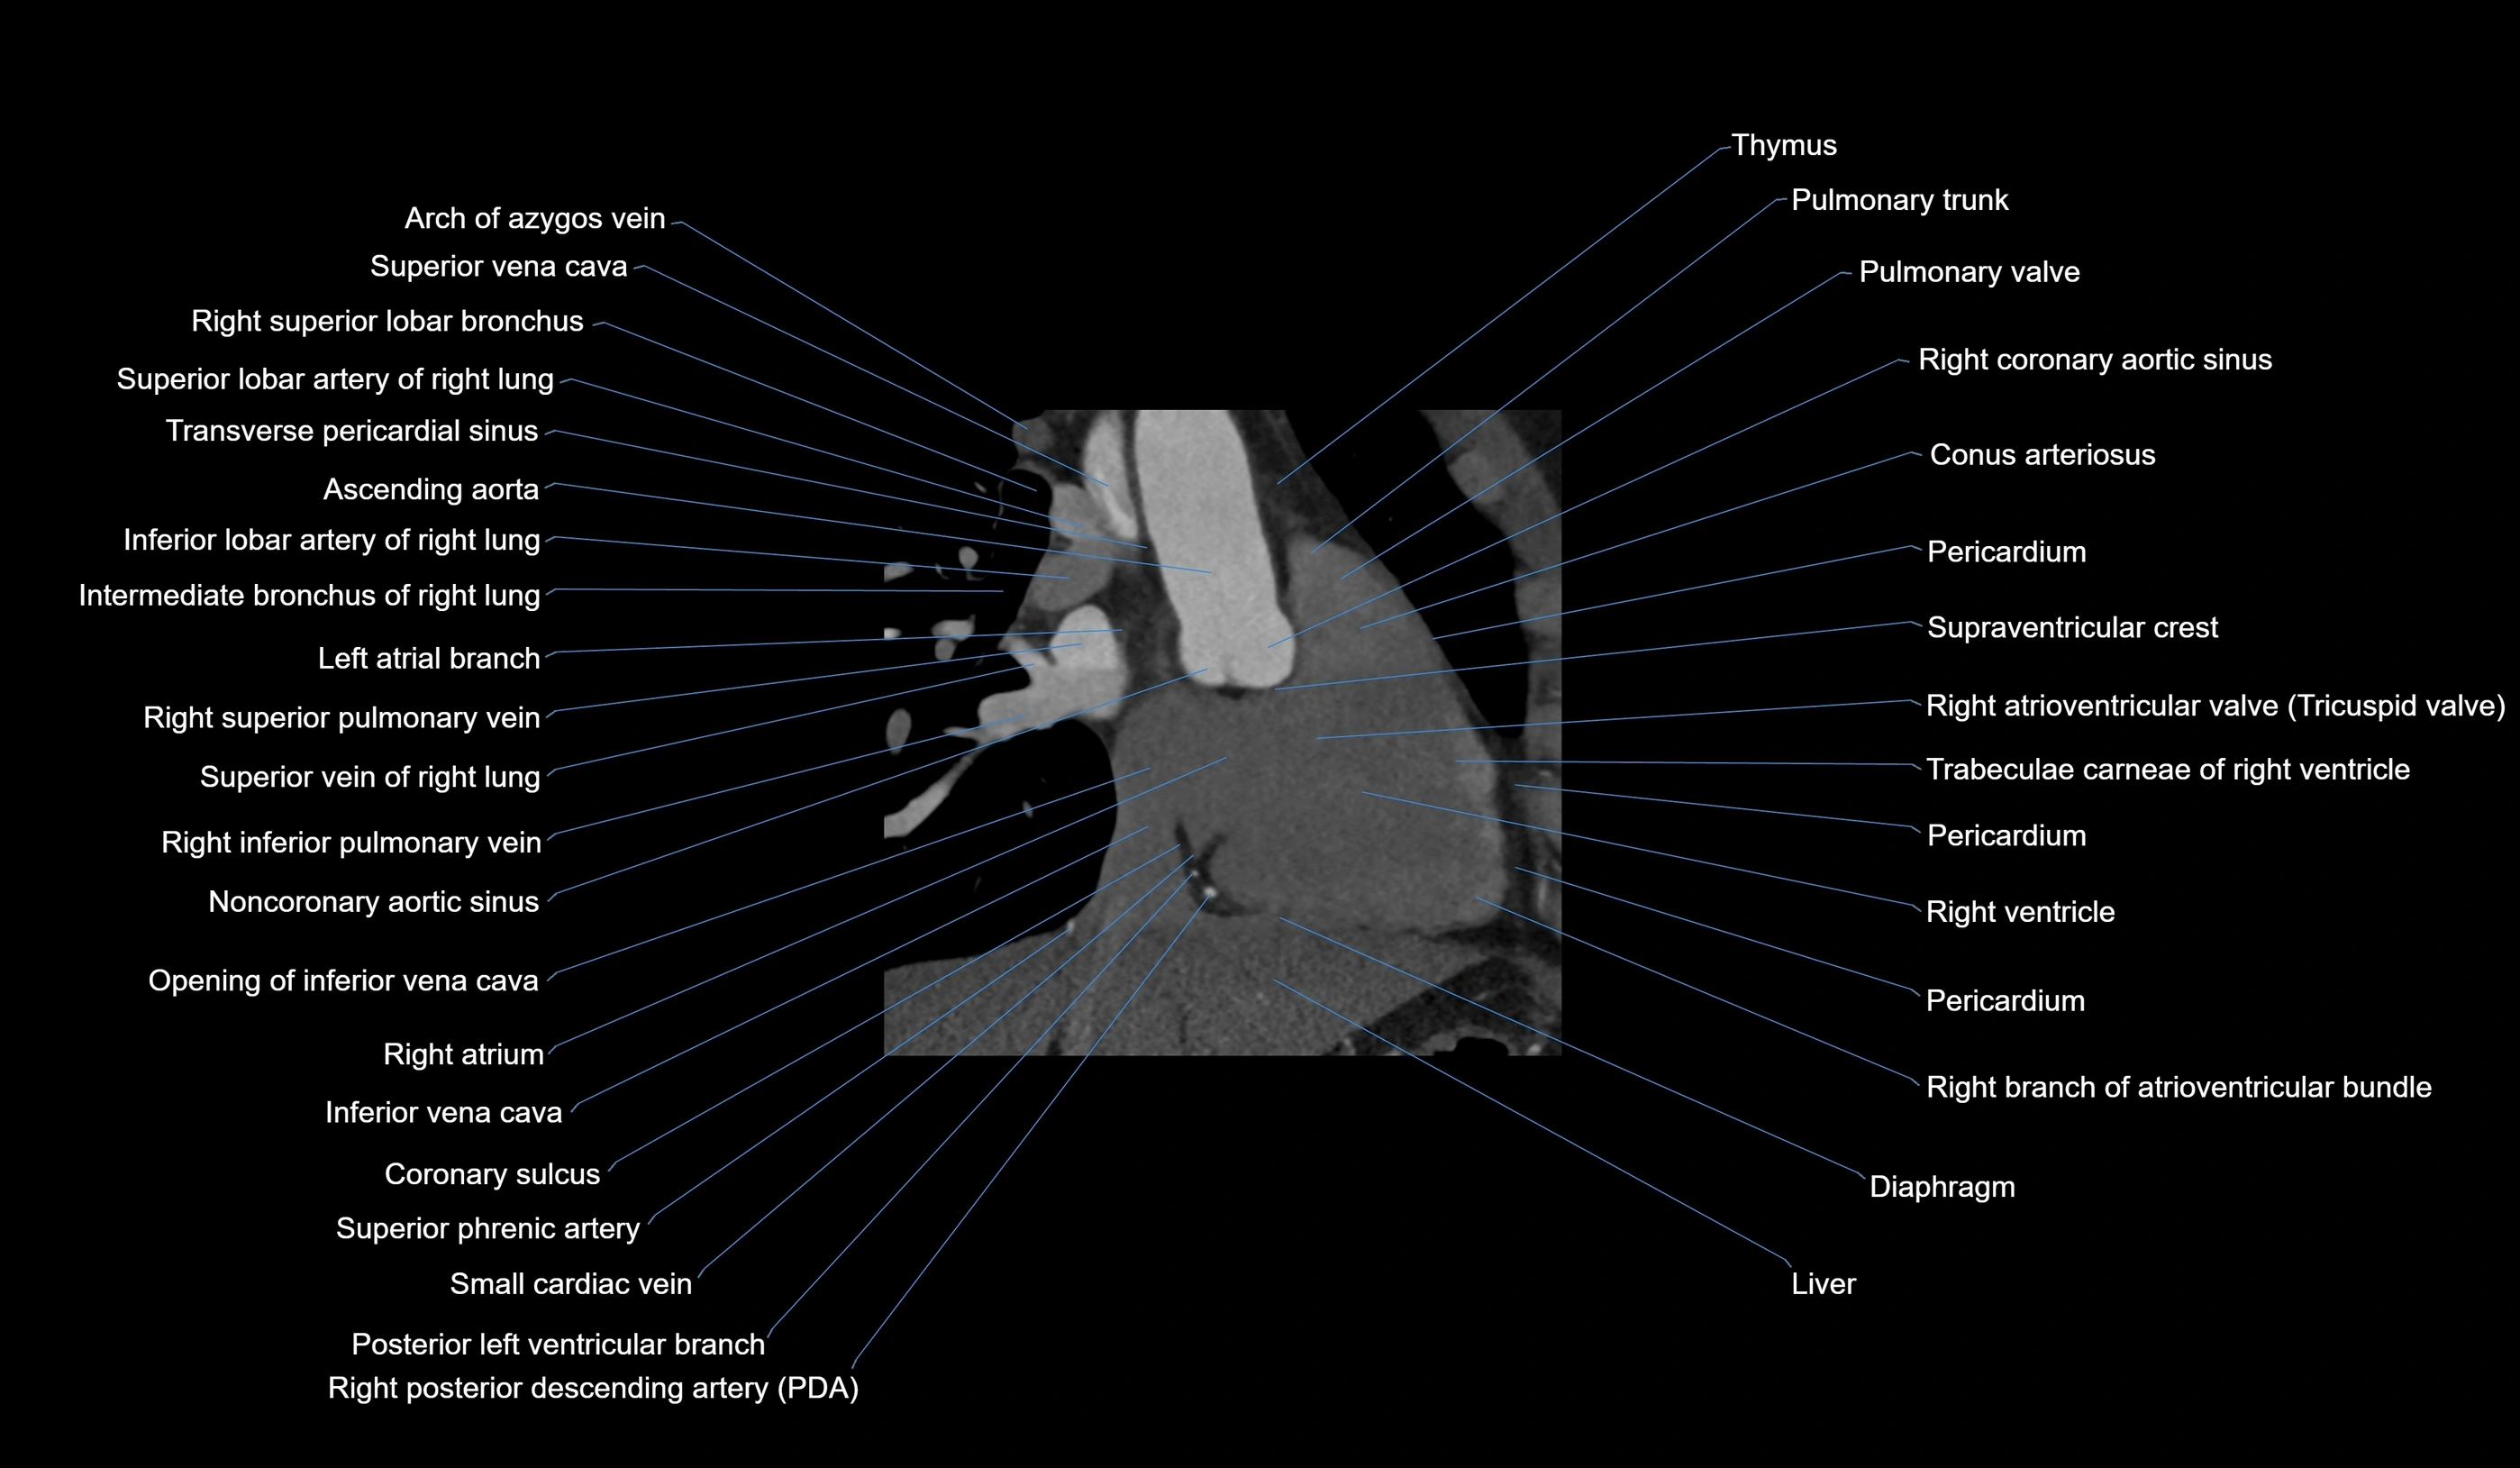

CT Coronary Angiography (CCTA):

Best non-invasive modality for acute marginal artery visualization

Shows origin, course along the acute margin, and right ventricular branches

Detects stenosis, occlusion, calcified and non-calcified plaques, aneurysm, or anomalous course

Multiplanar reformats and 3D reconstructions help in pre-PCI and surgical planning

Critical for assessing right ventricular infarction risk in RCA disease